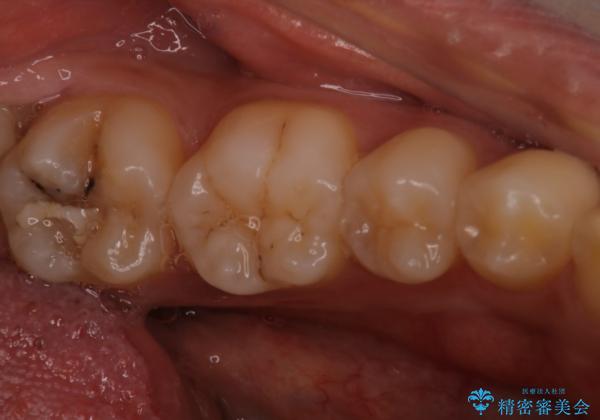

- 検査の結果、虫歯が見つかった患者様です。

白く目立たないものでの治療をご希望されたため、セラミックインレーでの治療となりました。

適合の良いセラミックインレーで修復することで見た目の綺麗さを保ったまま治療することができます。